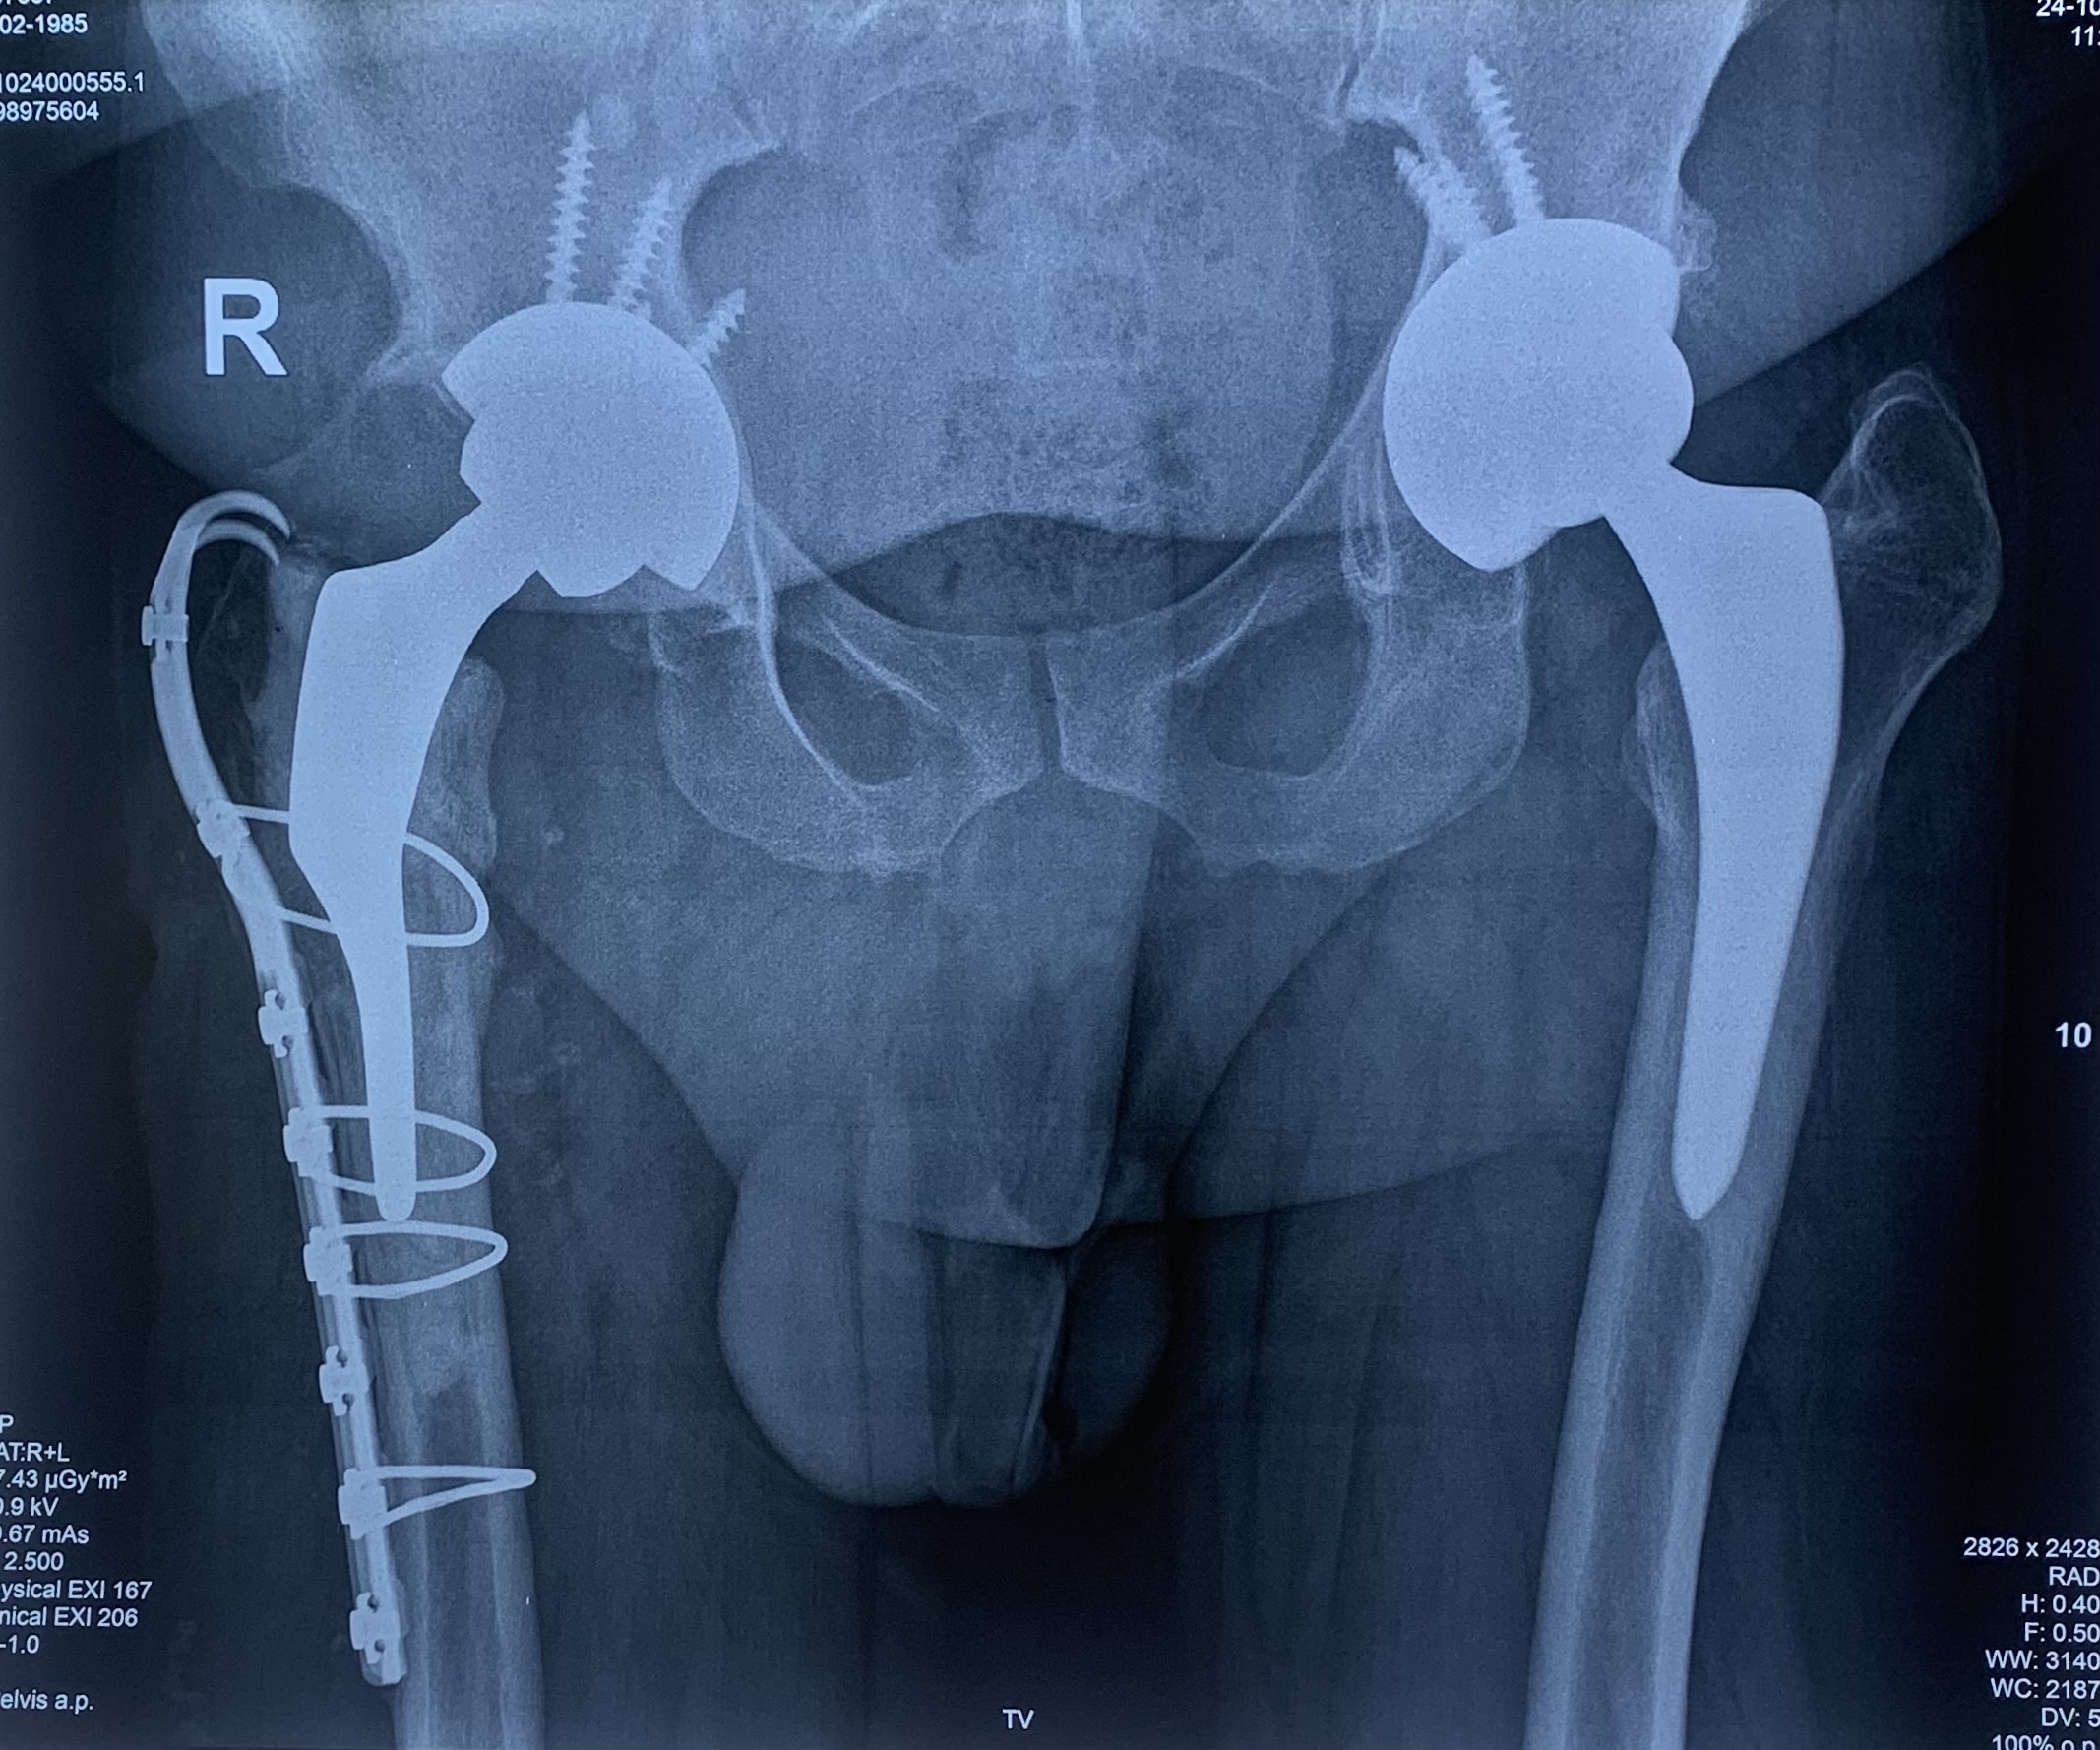

7. Πάσχω από σοβαρή αρθρίτιδα και στα δύο Ισχία. Μπορώ να χειρουργηθώ και στα δύο ισχία ταυτόχρονα;

Ο συνδυασμός της ελαχιστοποίησης του τραύματος (με όλα τα πλεονεκτήματα που προαναφέρθηκαν) και της ύπτιας θέσης του ασθενούς στο χειρουργείο, στο τραπέζι έλξης, διευκολύνει την επιλογή αυτή. Στην κλινική μας έχουμε πραγματοποιήσει σημαντικό αριθμό αρθροπλαστικών “δύο επεμβάσεις – μία αναισθησία”. Θα σας προτείνουμε την επιλογή αυτή αν η γενική υγεία σας το επιτρέπει, με κύριο μέλημα την ασφάλειά σας.

Στην εικόνα 6 βλέπουμε την προεγχειρητική ακτινογραφία άνδρα 56 ετών που υποβλήθηκε σε ταυτόχρονη αρθροπλαστική AMIS με navigation robotic assistance. Στην εικόνα 21 ο προεγχειρητικός τρισδιάστατος σχεδιασμός, αναλυτικά. Στην εικόνα 22 η πλοήγηση από το σύστημα διεγχειρητικά, με απόλυτη ακρίβεια και το άριστο τελικό ακτινολογικό αποτέλεσμα. Ο ίδιος ασθενής στην επανεξέταση, 24 μέρες μετά την επέμβαση στο ιατρείο.